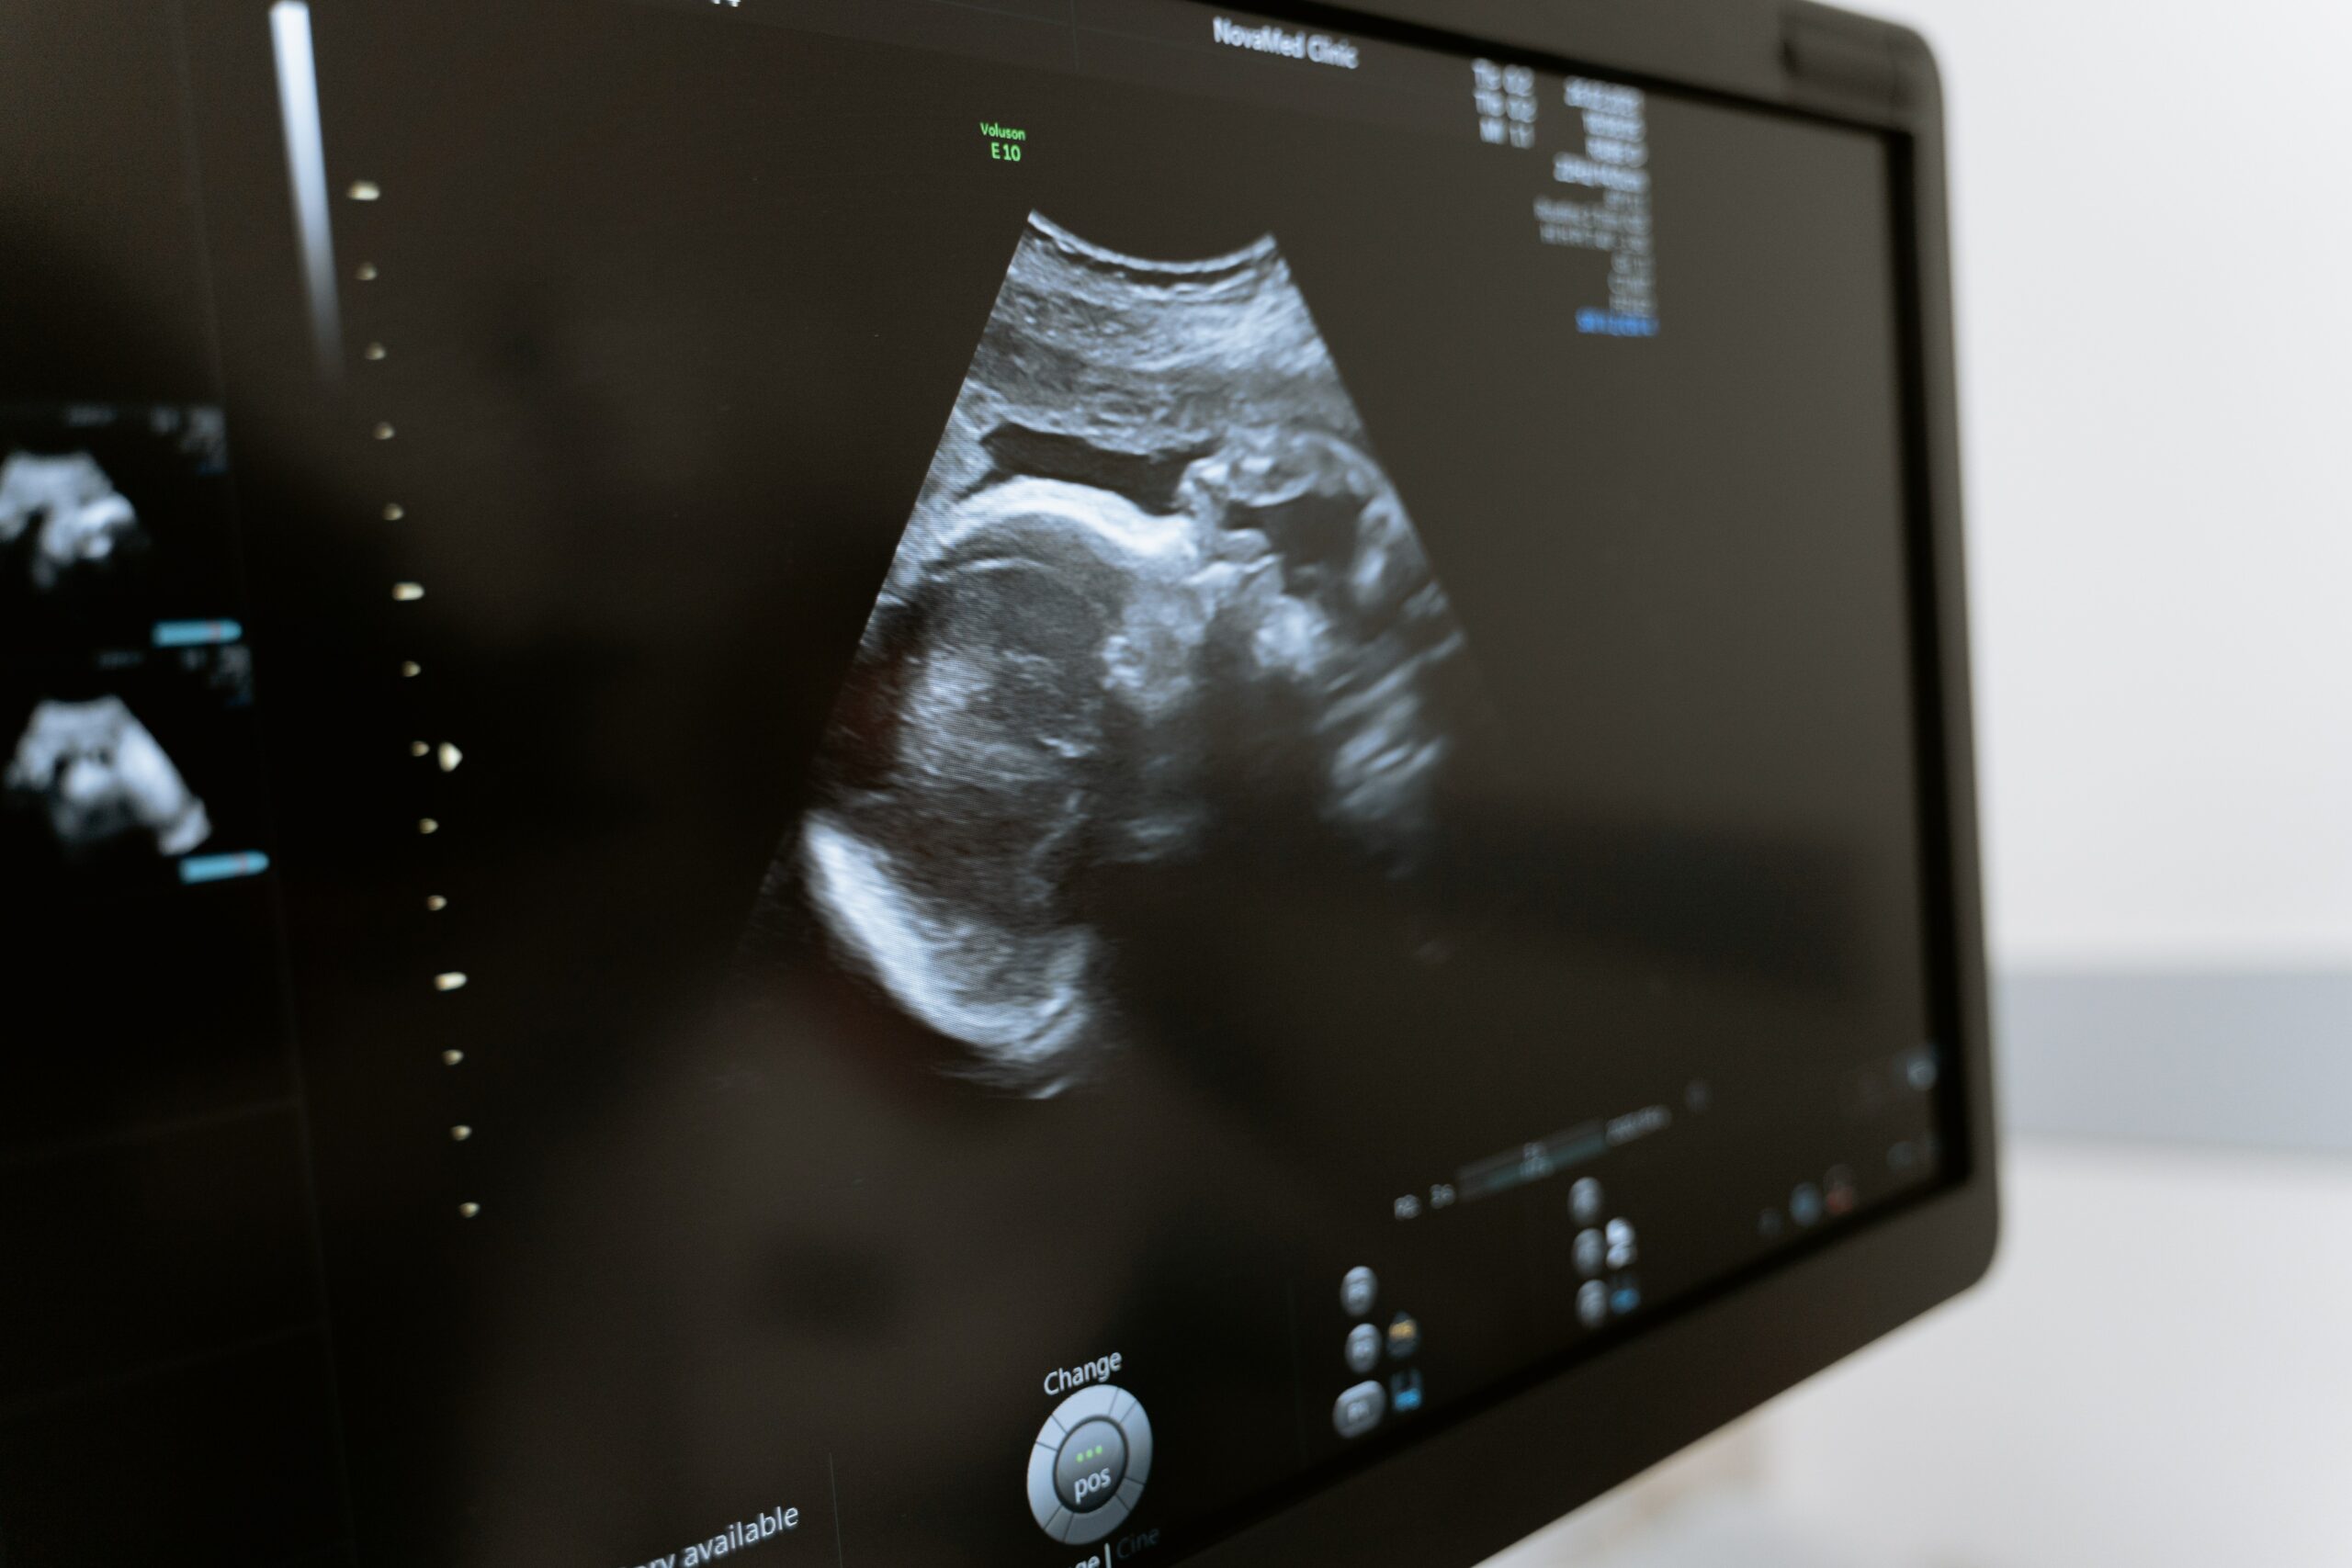

Al considerar sus opciones, muchas mujeres se preguntan cuándo puede sentir dolor su feto. Esto es lo que debes saber.

En esta fase, clavar una aguja en el estómago del bebé hace que se liberen hormonas del estrés. Esto indica que el feto puede sentir dolor definitivamente a principios del segundo trimestre. Sin embargo, muchos factores indican que el bebé puede sentir dolor antes. Más información sobre el embarazo precoz aquí.